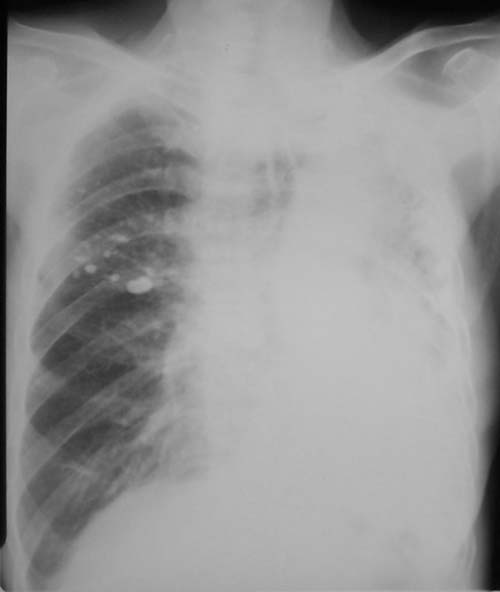

以下是引用jian-5587在2006-11-3 19:10:00的发言:[br]左侧胸廓塌陷,纵隔向左侧移位,左肺密度增高,但在上野见多发小斑片状气体密度影,左侧膈肌消失,考虑左肺占位所致肺不张可能性大,不排除左肺结核所致可能,建议进一步检查.右上肺陈旧结核病灶.

以下是引用jiangjing在2006-11-3 20:25:00的发言:[br]左侧胸廓塌陷,纵隔向左侧移位,左肺密度增高,但在上肺野可见部分含气肺组织影,左侧膈面消失,右上肺见多发班点状钙化灶,右肺代偿性肺气肿,右肺部分经纵隔疝入左侧胸腔,左侧胸膜增厚。考虑,肺结核致左肺毁损[肺硬化],右侧钙化灶,左侧胸膜增厚,右肺肺气肿。建议ct检查排除左肺新生物所致肺不张。

以下是引用dyqct在2006-11-3 21:48:00的发言:[br]支持:1、左肺结核致左肺毁损[肺硬化];[br] 2、右上肺陈旧性肺结核;[br] 3、建议ct进一步检查。